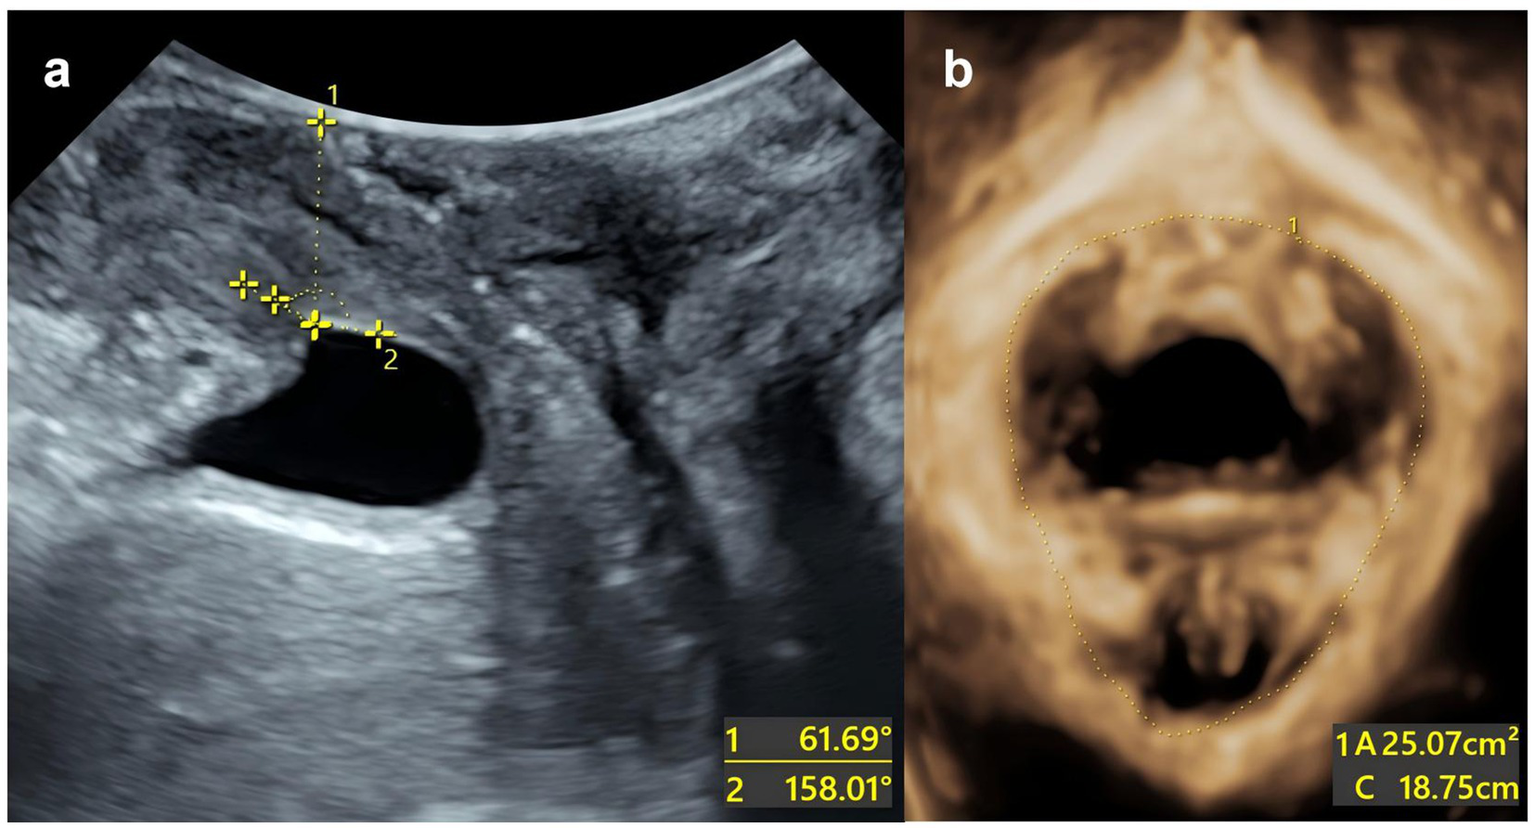

Example: The patient is a 27-year-old primipara who delivered vaginally with forceps-assisted delivery during labour. During the maximum Valsalva manoeuvre, the following measurements were taken: bladder neck position −3 mm; urethral rotation angle 92.8°; posterior bladder angle 158.01°; and levator ani muscle hiatus area 25.07 cm2. The total score was 220, which corresponds to a predicted risk of postpartum SUI of approximately >90% (Figure 5).

Figure 5

Split-screen image for genital hiatus at the maximum Valsalva maneuver. (a) The urethral inclination angle under maximum Valsalva manoeuvre is 61.69°. The posterior corner of the bladder under the maximum Valsalva manoeuvre is 158.01°. (b) The area of the levator ani muscle defect is 25.07 cm2.